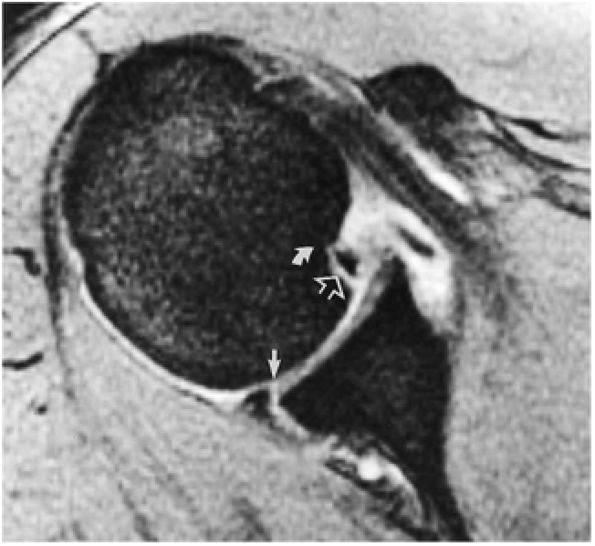

Axial FS PD FSE images are sensitive for the detection of small paralabral cysts as markers for labral tears.

A separate FS PD-weighted FSE sequence is used to increase sensitivity to fluid and to identify paralabral cysts, articular cartilage labral avulsions, and muscle edema (Fig. 8.4). FSE sequences are less sensitive to intralabral signal intensity in the spectrum of degenerations or tears unless there is imbibed fluid. FSE (FS PD FSE) images, however, are superior for the demonstration of labral morphology in cases of avulsions or contour abnormalities.